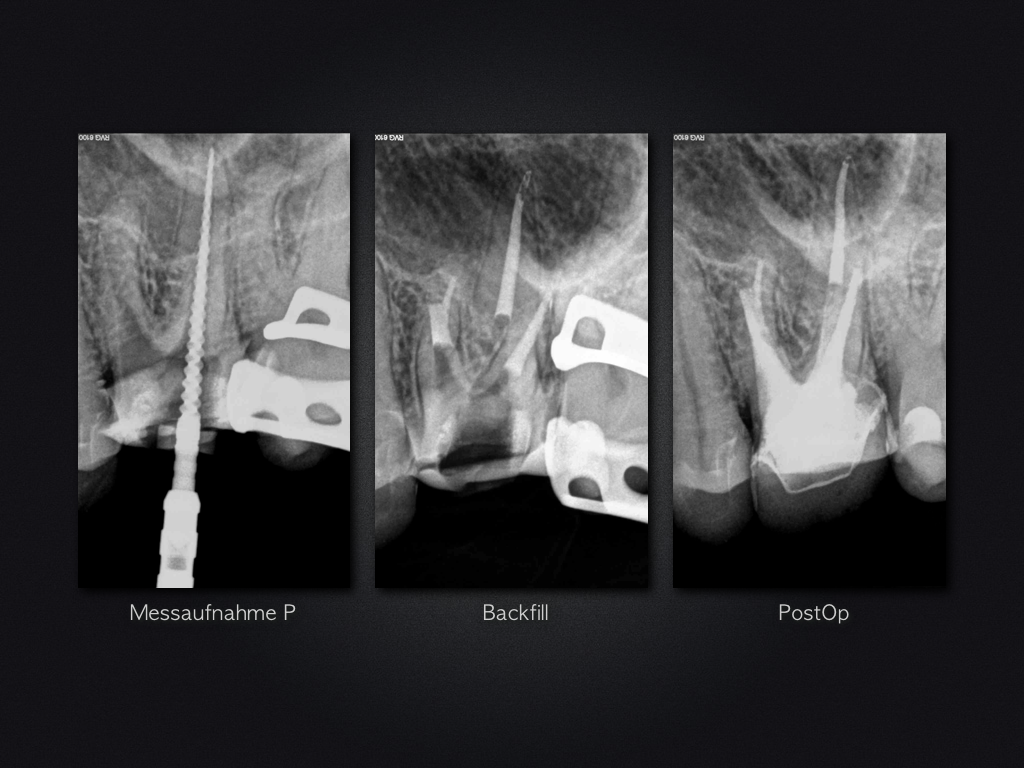

26D.006

Fette Stufe